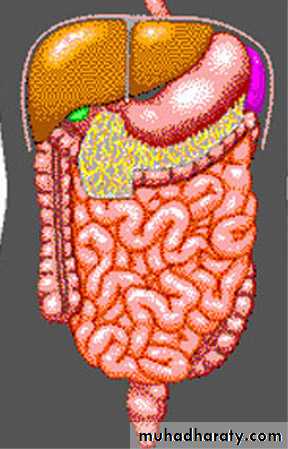

Anatomy

Large bowelperipheral

haustra

Small bowel

central

valvulae conniventes

Stomach

Liver

Pancreas

Ascending colon

Transverse colonStomach

Descending colon

Sigmoid colon

RectumHaustra

Valvulae conniventes:

mucosal folds thatgo right across small bowel

peripheral

haustra± faeces

larger calibre (>5cm<9cm)

no faeces

smaller calibre

(2-2.5cm)

Large versus small bowel on AXR

Large bowel Small bowel